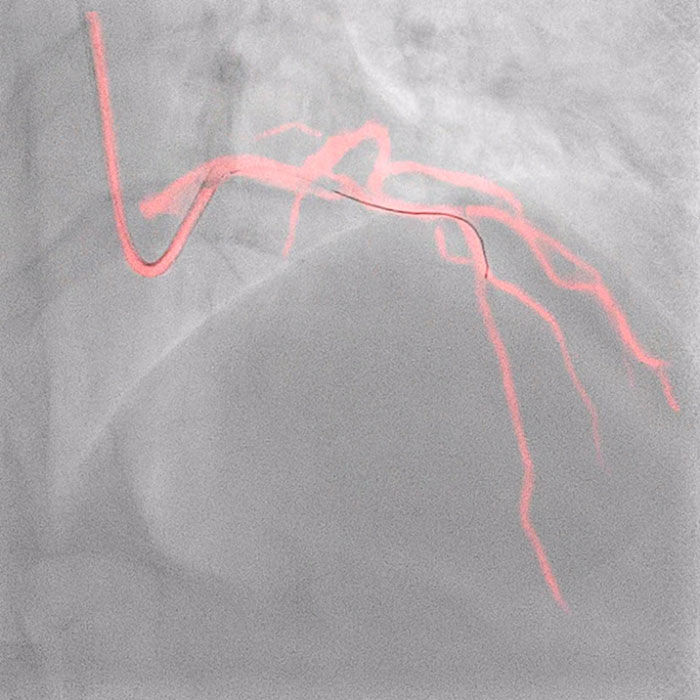

El software Dynamic Coronary Roadmap de Philips es una innovación de visualización en tiempo real que elimina la necesidad de inyectar medios de contraste adicionales al superponer el angiograma sobre imágenes fluoroscópicas 2D compensadas por movimiento en tiempo real para proporcionarle a los intervencionistas retroalimentación visual continua sobre el posicionamiento de los cables guía y los catéteres. Como complemento de esta tecnología, el sistema de guía de precisión Philips IntraSight agiliza la evaluación de lesiones, simplifica conocer el tamaño de los vasos, permite la administración precisa de la terapia y también apoya al operador en su objetivo de reducir los volúmenes de contraste.

Philips Dynamic Coronary Roadmap